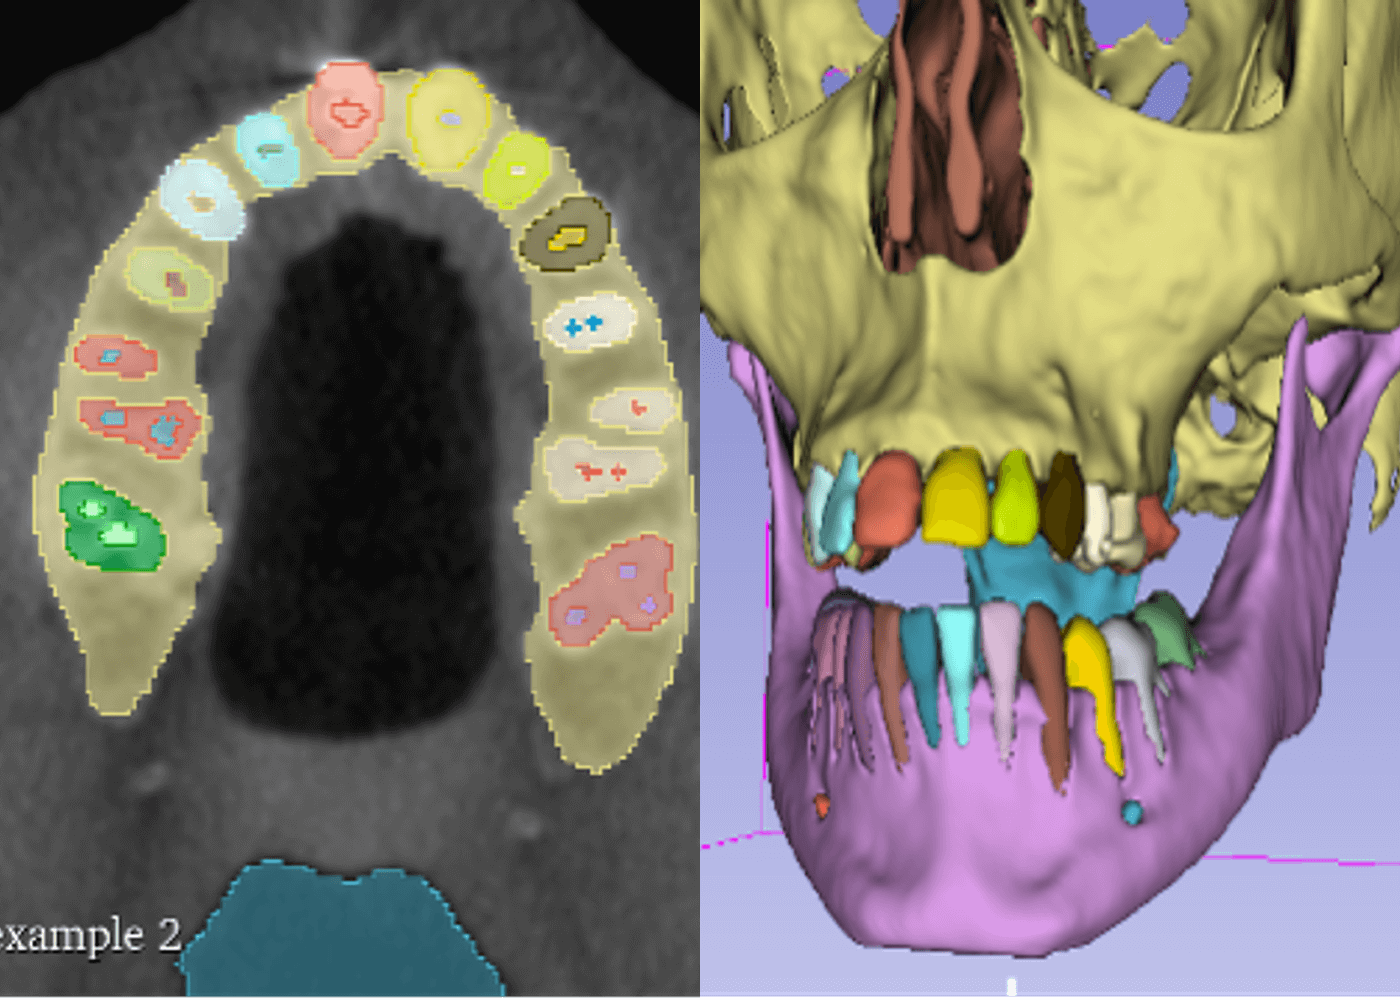

radiology

Dental cone beam CT structures segmentation